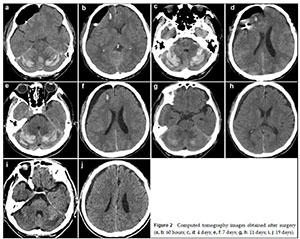

20170712151136  Figure 2 Computed tomography images obtained after surgery (a, b: 60 hours; c, d: 4 days; e, f: 7 days; g, h: 11 days; i, j: 19 days).